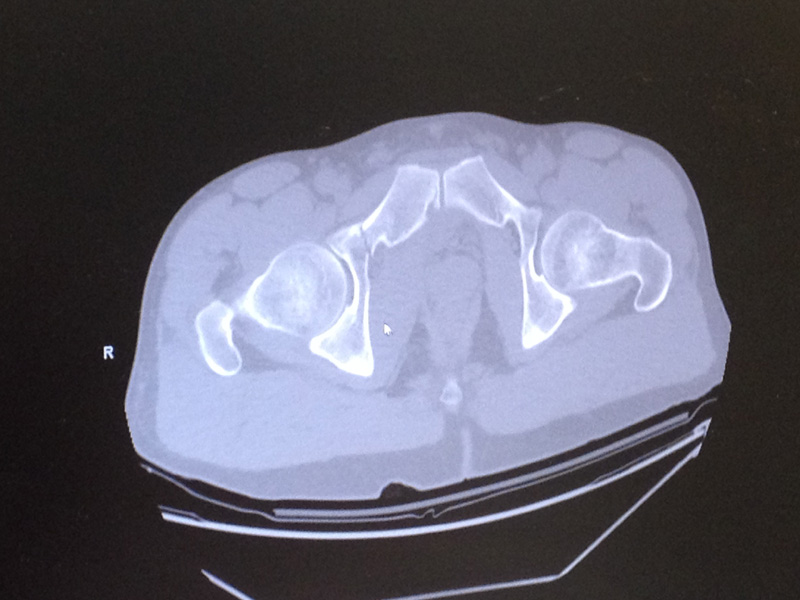

As the blog says: “What started out like any other Saturday, complete with shuttles and riding with buddies out at the Ranch, ended with a bam and a crunch like something out of a Roadrunner cartoon when Mark Weir and four friends attempted to clear a downed tree limb that had fallen across one of the trails in a previous storm. As a result, Weir sustained a broken sacrum and fractured his pelvis in three places.”

Weir’s pelvis was broken in three places and it took the ingenuity of his riding pals, including enduro-racer Ben Cruz, to gingerly carry Weir down from out of the trees on a home-made backboard made from a bit of plywood, to the point where the Novato Fire Department could get him stabilised and off to hospital. He’s now back home, under orders to have six to eight weeks of bed rest.